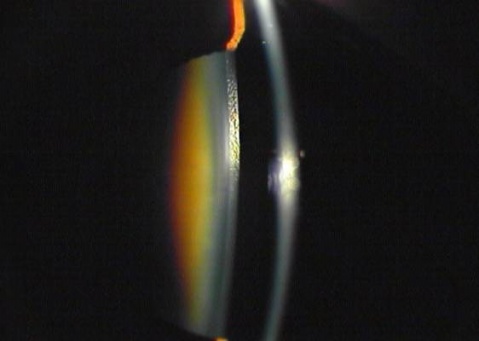

(2)膨胀期(intumescent stage):又称未熟期(immature stage)。晶状体混浊继续加重时,渗透压改变,在短期内有较多水份积聚,晶状体急剧肿胀,体积变大,将虹膜向前推移,前房变浅,可诱发急性闭角型青光眼。晶状体呈不均匀的灰白色混浊,在裂隙灯下仍可看到皮质内的空泡、水裂和板层分离。视力明显减退,眼底难以看清。